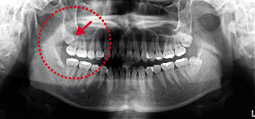

診断例①

右上の一番奥に親しらずがあり、歯肉の下に斜めに傾斜し、

完全に埋まっている状態でした。

手前の歯の根の先に歯冠が入り込んでおり、抜歯が困難なことが予想されます。

CT撮影により断面(赤線)でより詳しく診断することになりました。